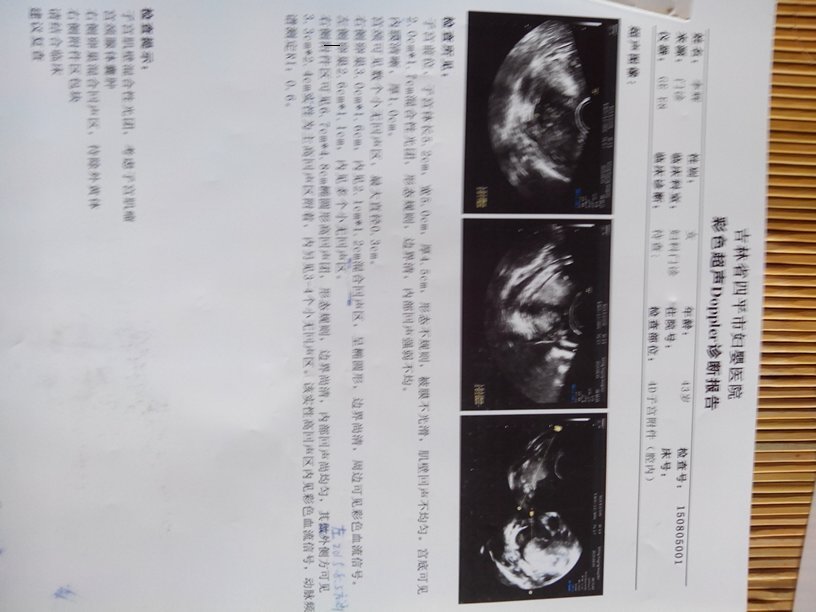

右侧附件卵巢区不均实质性回声你好大夫,我今年43岁,13年查出子宫肌瘤1.2*2.4厘米,其他正常右侧附件卵巢区不均实质性回声你好大夫,我今年43岁,13年查出子宫肌瘤1.2*2.4厘米,其他正常,然后14年三月复查子宫肌瘤多发最大的两厘米多,但是左侧附件可见4.8*4.1厘米类实质性回声,筛查卵巢肿瘤标志物正常,14年七月查左卵巢内测见5.3*4.0偏强实质性不均质性块状回声,边界尚清晰,形态尚规则有包膜,期内可见较丰富血流信号。15年8月检查右侧附件区可见6.7*4.8椭圆形高回声团,形态规则,边界尚清,内部回声尚均匀,其左外侧方可见3.3*2.4实性为主高回声区附着,内见3-4个小回声区,该实性高回声区内见彩色血流信号,然后例假过后七八天查子宫左上方不均质回声6.3*5.3㎝,期内见少许血流信号,怎么有时候在左侧有时候在右侧呢,还有位置有时在卵巢有时在附件,也不一样,而且最后一次大夫说位置还不确定,到底是左侧还是右侧,具体位置到底在哪里呢,还有就是良性面大恶性面大呢。